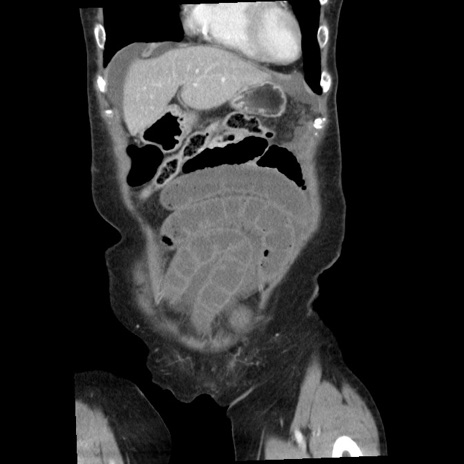

症例1(冠状断像)

【症例】80歳代女性

【主訴】腹痛

【現病歴】8時間前から腹痛あり来院。

【既往歴】糖尿病、脂質異常症、子宮体癌にて子宮全摘術

【身体所見】意識清明・会話良好だが腹痛で苦悶様、全腹部にわたって反跳痛と圧痛あり

【データ】WBC 13600、CRP 0.14、LDH 224、CK 90